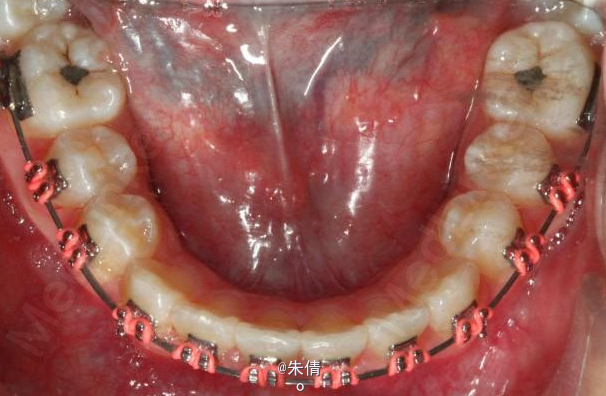

对于面型较好,拥挤度不大的病例,推磨牙向后不失为一种很好的方法,当然现在推磨牙后向的手段和方法很多,但是主要 是适应证的问题。我认为我们在做推磨牙向后,首先是考虑拥挤度,第二个要考虑的是现有的面型,第三点也是很重要的一点,是考虑牙弓后段拥挤度,Tweed-Merryfireld拥挤度的诊断方法将牙弓拥挤度分析分为三段,牙弓前段拥挤度,牙弓中段的拥挤度,以及牙弓后段的拥挤度。不管用什么方法或是手段推磨牙向后,一定不能将牙弓前端矛盾移到牙弓中段或是后段。今天给大家看一直面型,拥挤度不是很大推磨牙向后的病例。希望对大家能有所帮助。